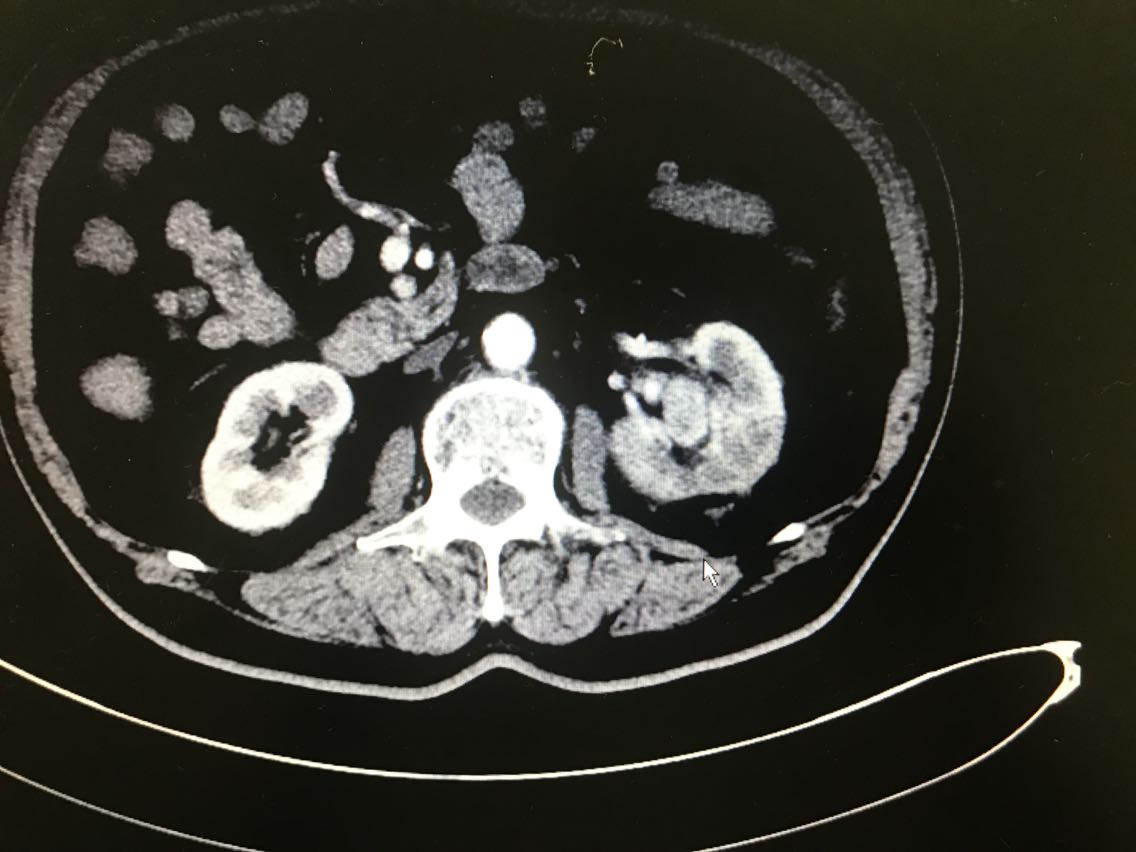

患者男性,81岁。 主诉:血尿伴左侧腰痛一月余 现病史:患者一月前出现血尿,伴左侧腰痛,于当地医院就诊,诊断为左侧肾盂占位。患者为求进一步治疗来我院门诊,门诊以肾盂恶性肿瘤收入院。起病以来,患者睡眠饮食尚可,二便无明显改变,体重未减。 既往史无特殊。

查体无特殊。 辅助检查: 全腹CT示:左肾上极肿块,侵犯左肾上盏并突入左肾盂,性质:左肾细胞癌可能性大,肾盂癌待排,结合临床。

诊断:左肾占位:肾盂癌? 治疗:腹腔镜左肾盂癌根治术